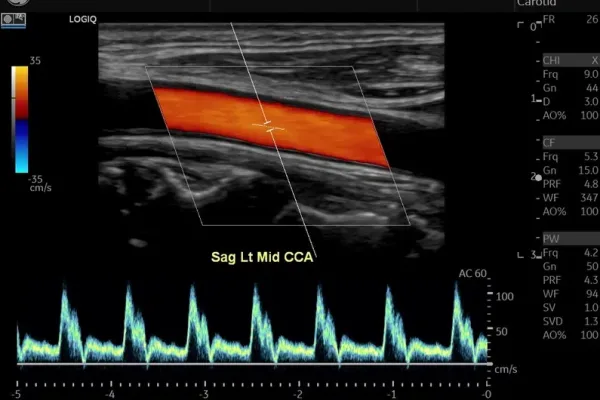

Échographie GE LOGIQ S8